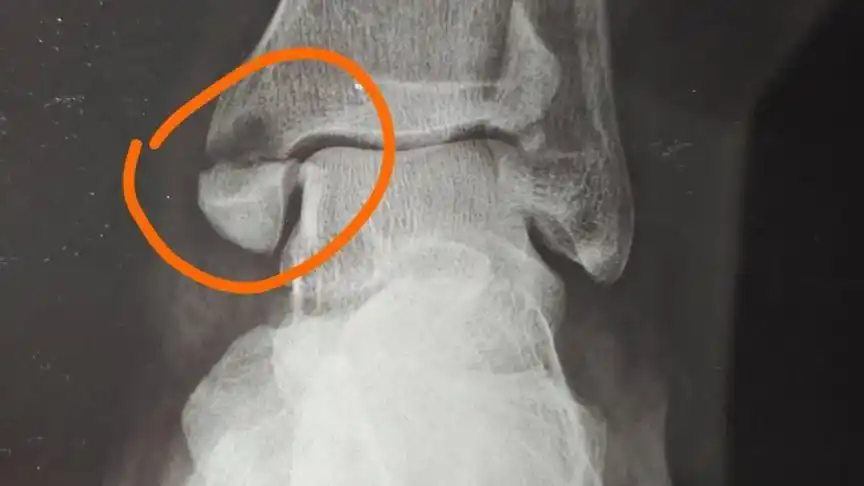

脚内踝骨折片子

今天洗澡的时候发现脚内踝处肿了,如图圆圈的部分,长方形的部分为疼痛